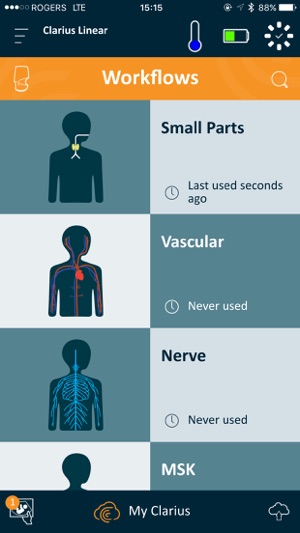

Clarius is the only Handheld Wireless Ultrasound Scanner that doesn’t compromise on image quality. Designed as a Point-and-Shoot Ultrasound™ system, it has automated and optimized gain and frequency settings to capture images quickly. Or you can easily use manual settings to adjust images to your liking.

Our multipurpose Clarius C3 ultrasound scanner is designed to image the abdomen and lungs; it also works as a virtual phased array for quick scans of the heart. The Clarius L7 linear scanner is ideal for guiding procedures such as nerve blocks and targeted injections. For more information about Clarius Scanners, please visit www.clarius.com.